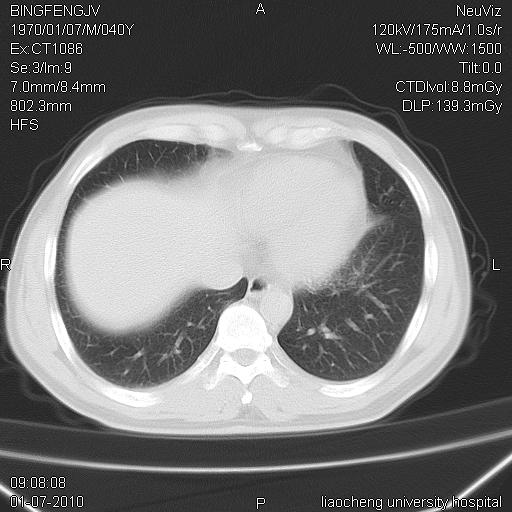

标题: CT23764B:男 40 肺部CT [打印本页]

标题: CT23764B:男 40 肺部CT

治疗2周后

考虑左肺上叶近胸膜下炎症并肺气囊形成。

炎症,大部吸收。